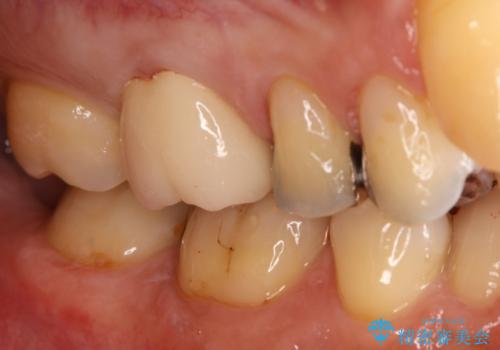

最新の症例

Latest cases